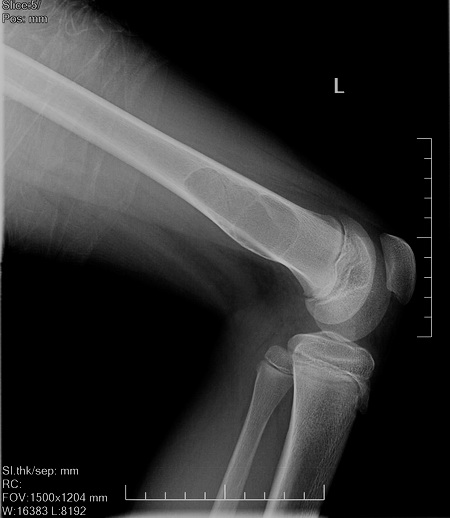

男,13岁,因膝关节外伤来照片,伤前无症状。

干骺端病变,透光度较高,有明显硬化边,内多房分隔,无明显钙化,可见骨皮质裸露征,无骨膜反应及软组织肿块,男13岁,考虑良性肿瘤样病变,多房性骨囊肿可能。

鉴别:abc、nof、软黏纤、囊性骨纤。

建议ct。